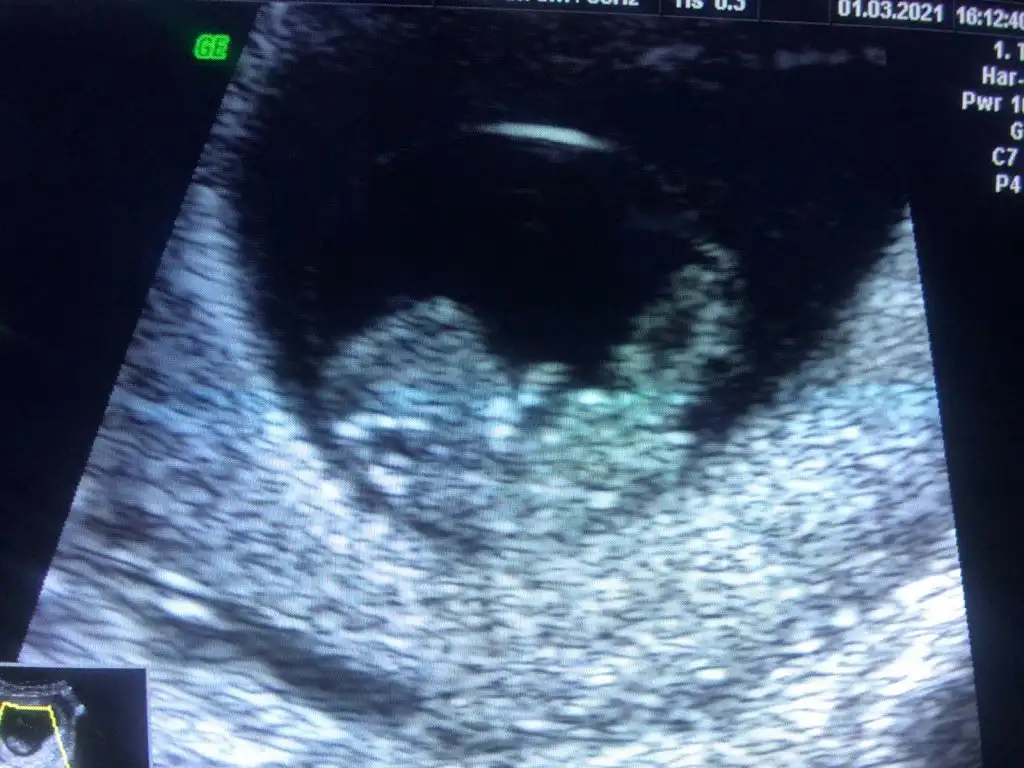

merhaba kızlar bu bebeğimin 9 haftalık karından ultrason resmî daha önce 6 haftalık halini atmıştım ramzi teorisi için erkek dediler hep başka profillerde deama doktorum ramziye göre plasentanın yerine bakılır kız gbi dedi doktorları böyle tahminde bulunanlar yada ramzi teorisi tutanlar var mi

Bi doktorun bu teoriyi bilmesine hem şaşırdım hem sevindimEki Görüntüle 2794519